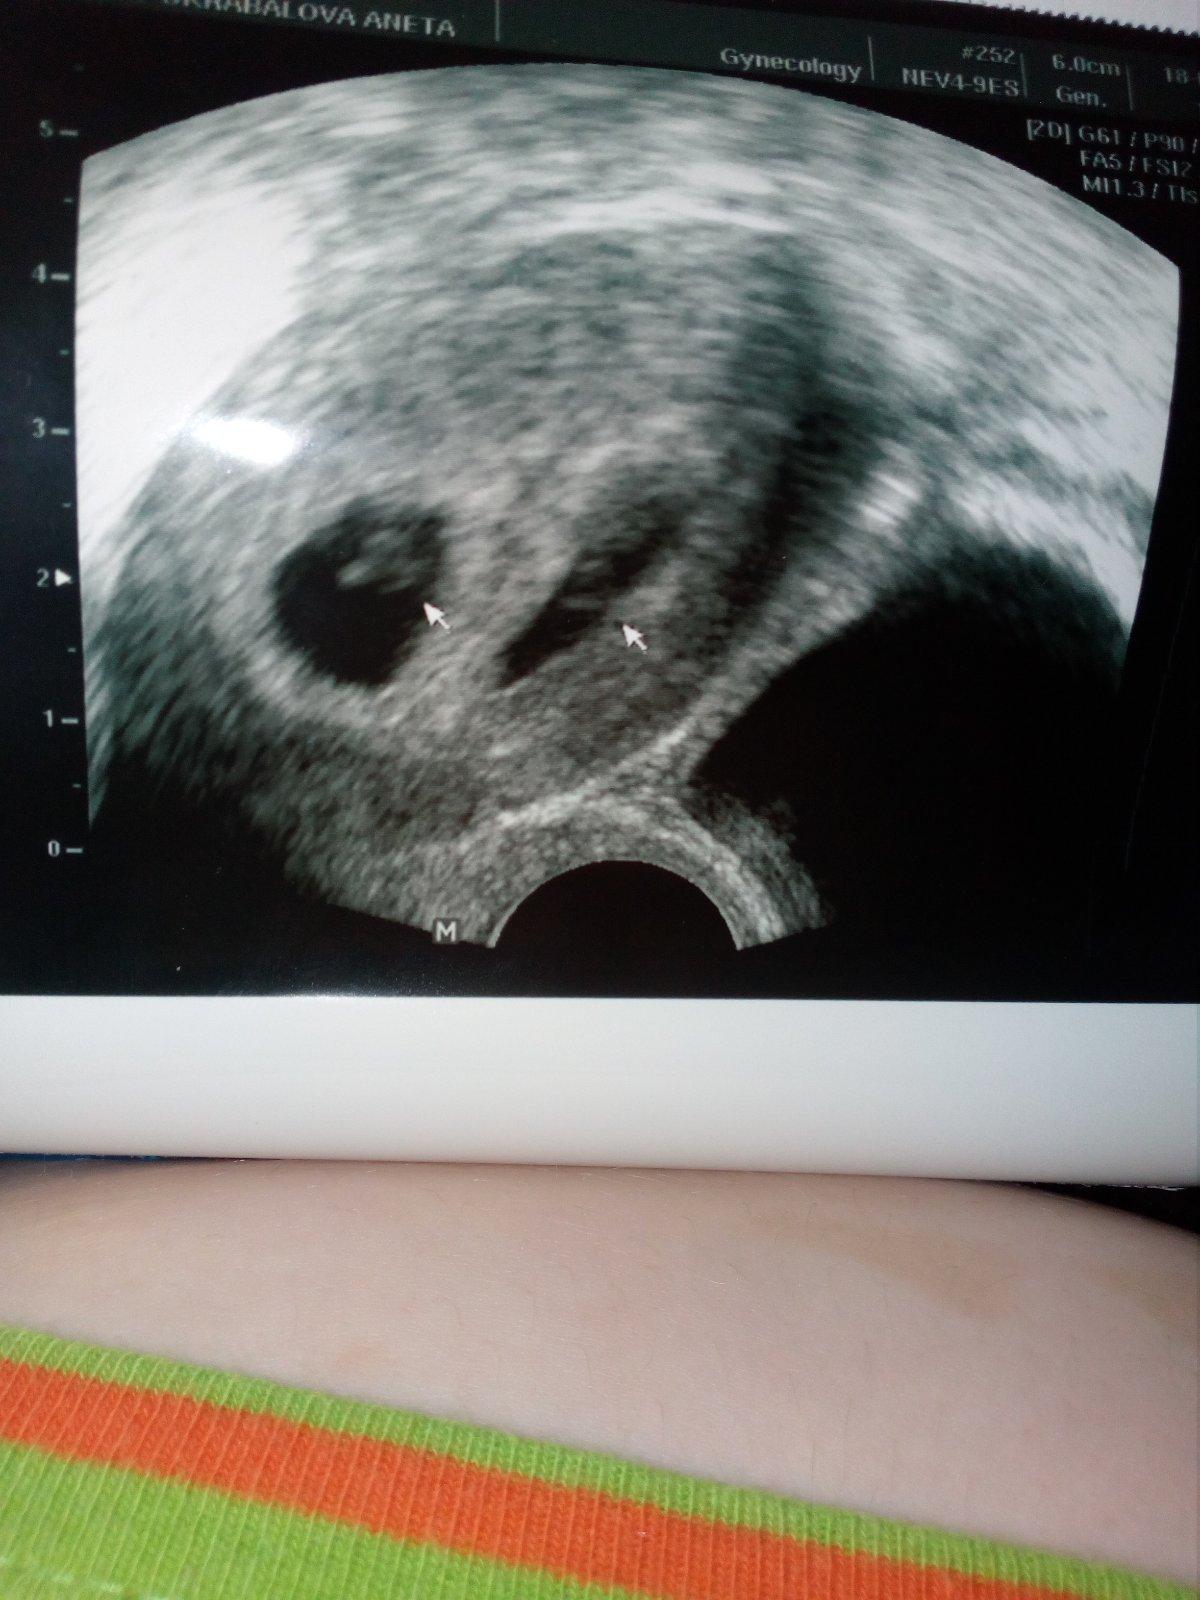

Já byla taky na ko a teda váček jsme viděli, jsem v 5+0, ale dr. nebyl vůbec spokojený s umístěním těhotenství, vypadá to na roh děložní, což je tak 50/50 😔 snažím se být optimistická, ale bojím se. Jsem na neschopence a v pondělí na další ko, jak se to bude dál vyvíjet. Nemáte s tím někdo zkušenost že to dopadlo nakonec dobře a mimčo rostlo do dělohy a ne směrem k vejcovodu???